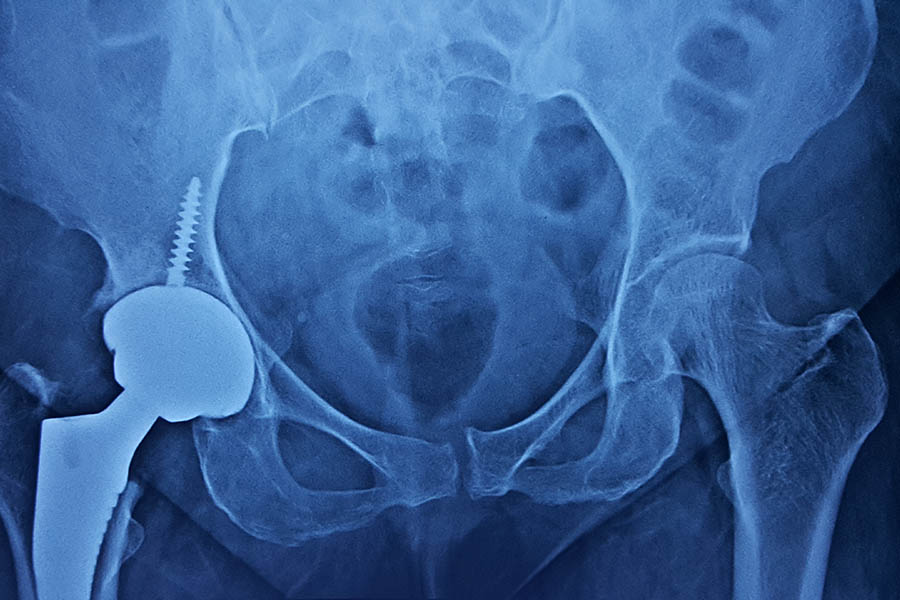

Total Hip Replacement

Case 1